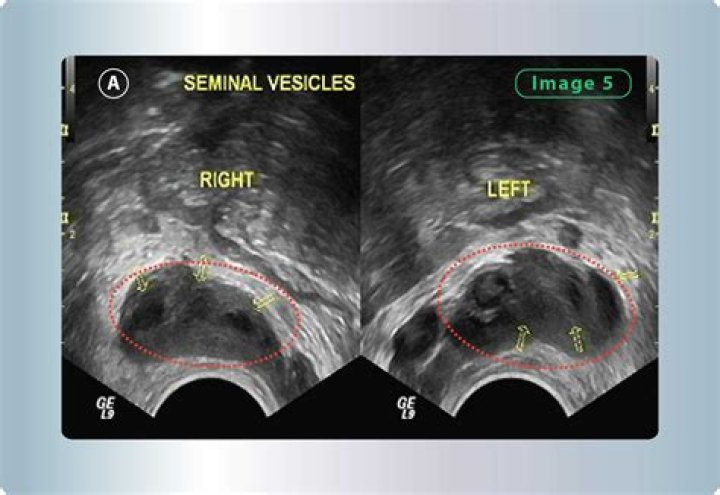

How is seminal Vesiculitis diagnosed?

Seminal vesiculitis is inflammation and/or infection of one or both vesicular glands. Signs may include purulent material contaminating bull semen. Diagnosis often occurs during a breeding soundness examination through manual rectal palpation or visible observation with rectal ultrasound of enlarged seminal vesicles.